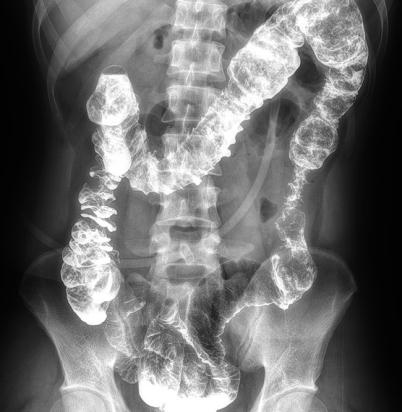

多功能動態(tài)平板DR,采用U型臂結(jié)構(gòu),具有靜態(tài)DR攝影、數(shù)字透視、數(shù)字造影和可視化攝影的功能。

電動旋轉(zhuǎn)內(nèi)平衡結(jié)構(gòu),可實現(xiàn)快捷擺位,滿足特殊體位的靜態(tài)與動態(tài)檢查。